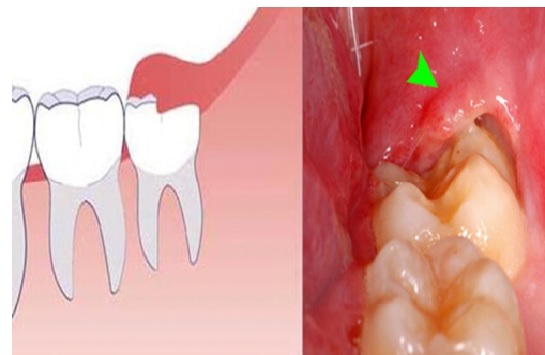

Viêm lợi trùm (Pericoronitis): Đây là biến chứng thường gặp nhất của răng khôn mọc lệch hoặc mọc bán phần. Khi răng chỉ trồi lên một phần khỏi lợi, phần lợi phủ phía trên tạo thành “túi lợi trùm”, dễ tích tụ thức ăn và vi khuẩn. Người bệnh có thể xuất hiện các biểu hiện như đau vùng răng khôn, sưng nướu, khó há miệng, hôi miệng hoặc sốt nhẹ. Nếu không được điều trị kịp thời, tình trạng viêm có thể lan rộng sang vùng má, góc hàm hoặc gây nhiễm trùng vùng hàm mặt.

.jpg)

Hình ảnh Viêm lợi trùm do răng khôn